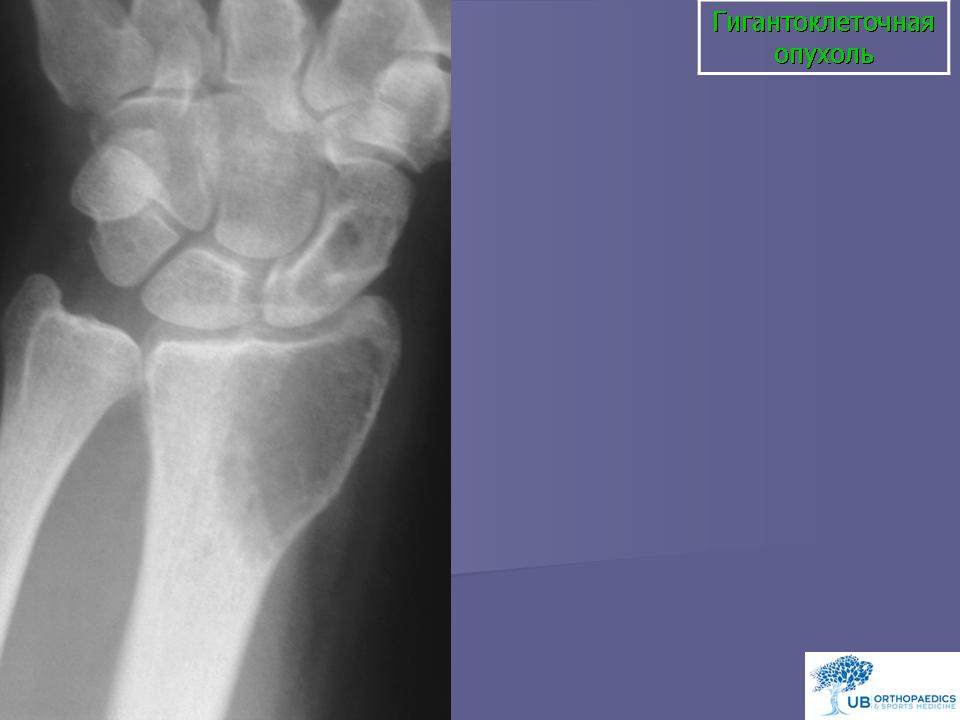

Гигантоклеточная опухоль.